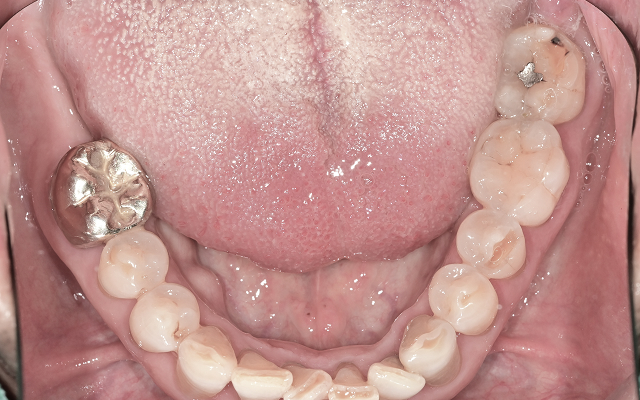

진료 전 구강 스캔과 구내 촬영을 통해

치아 상태를 꼼꼼하게 분석하고 설명드립니다.

엑스레이, 구강 사진, CT 등을 통해 꼼꼼히 진단하고 촬영한 사진을 함께 보며 쉽게 이해하실 수 있도록 설명드립니다.